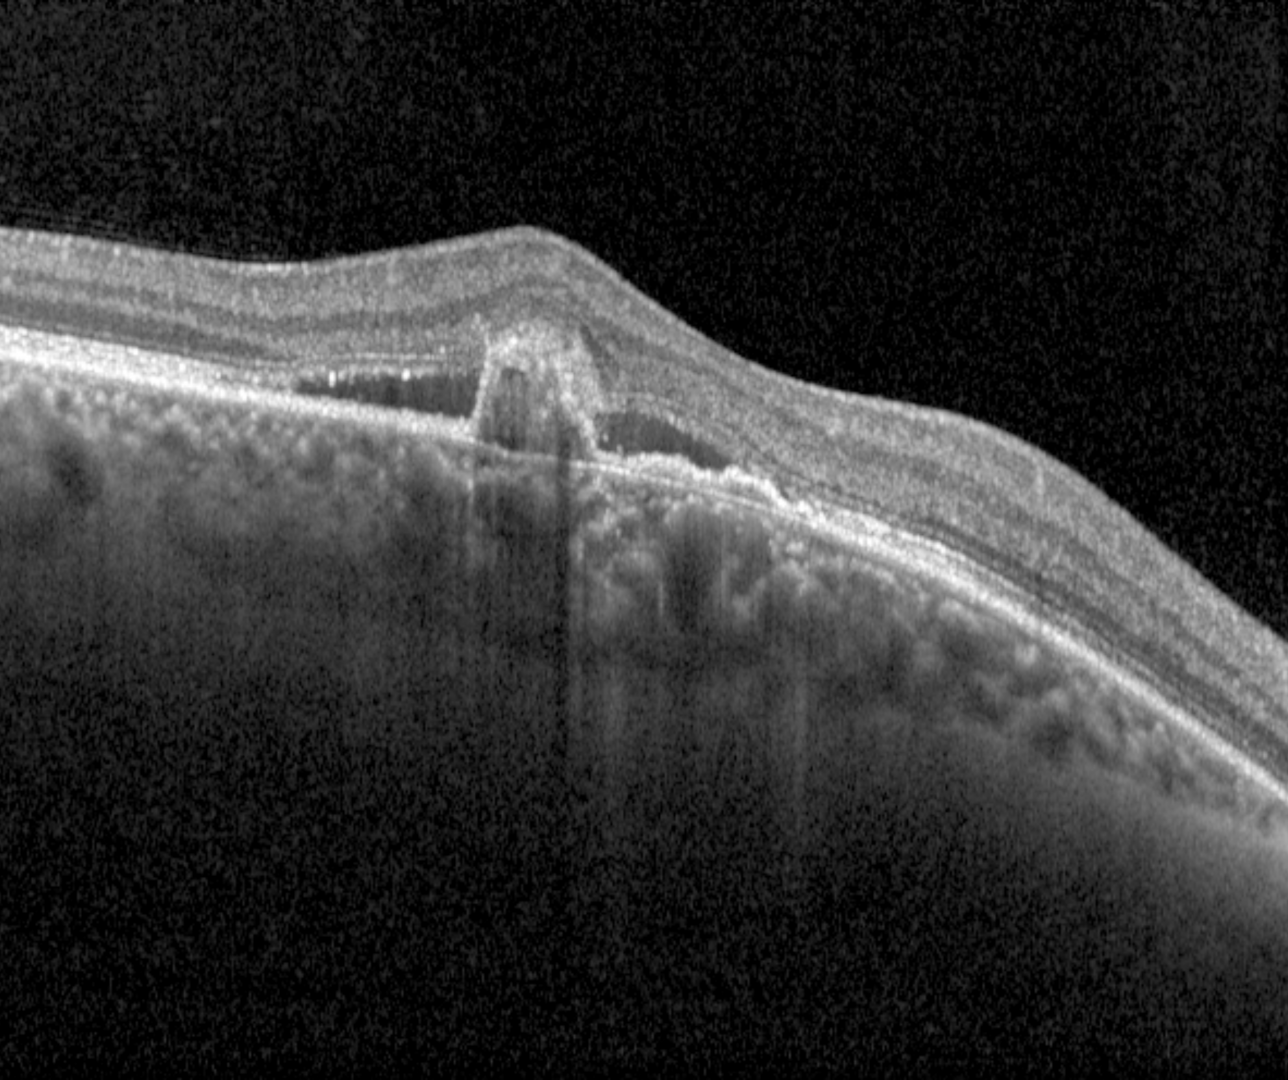

OCT shows multilobular PEDs with the peaked, thumb-like or notched component corresponding to the polypoidal lesion and the flat irregular PED harbours the type 1 neovascularisation.

Spectralis OCT line scans (right eye)

Spectralis OCT line scans (right macula)

Spectralis OCT line scans (left macula)